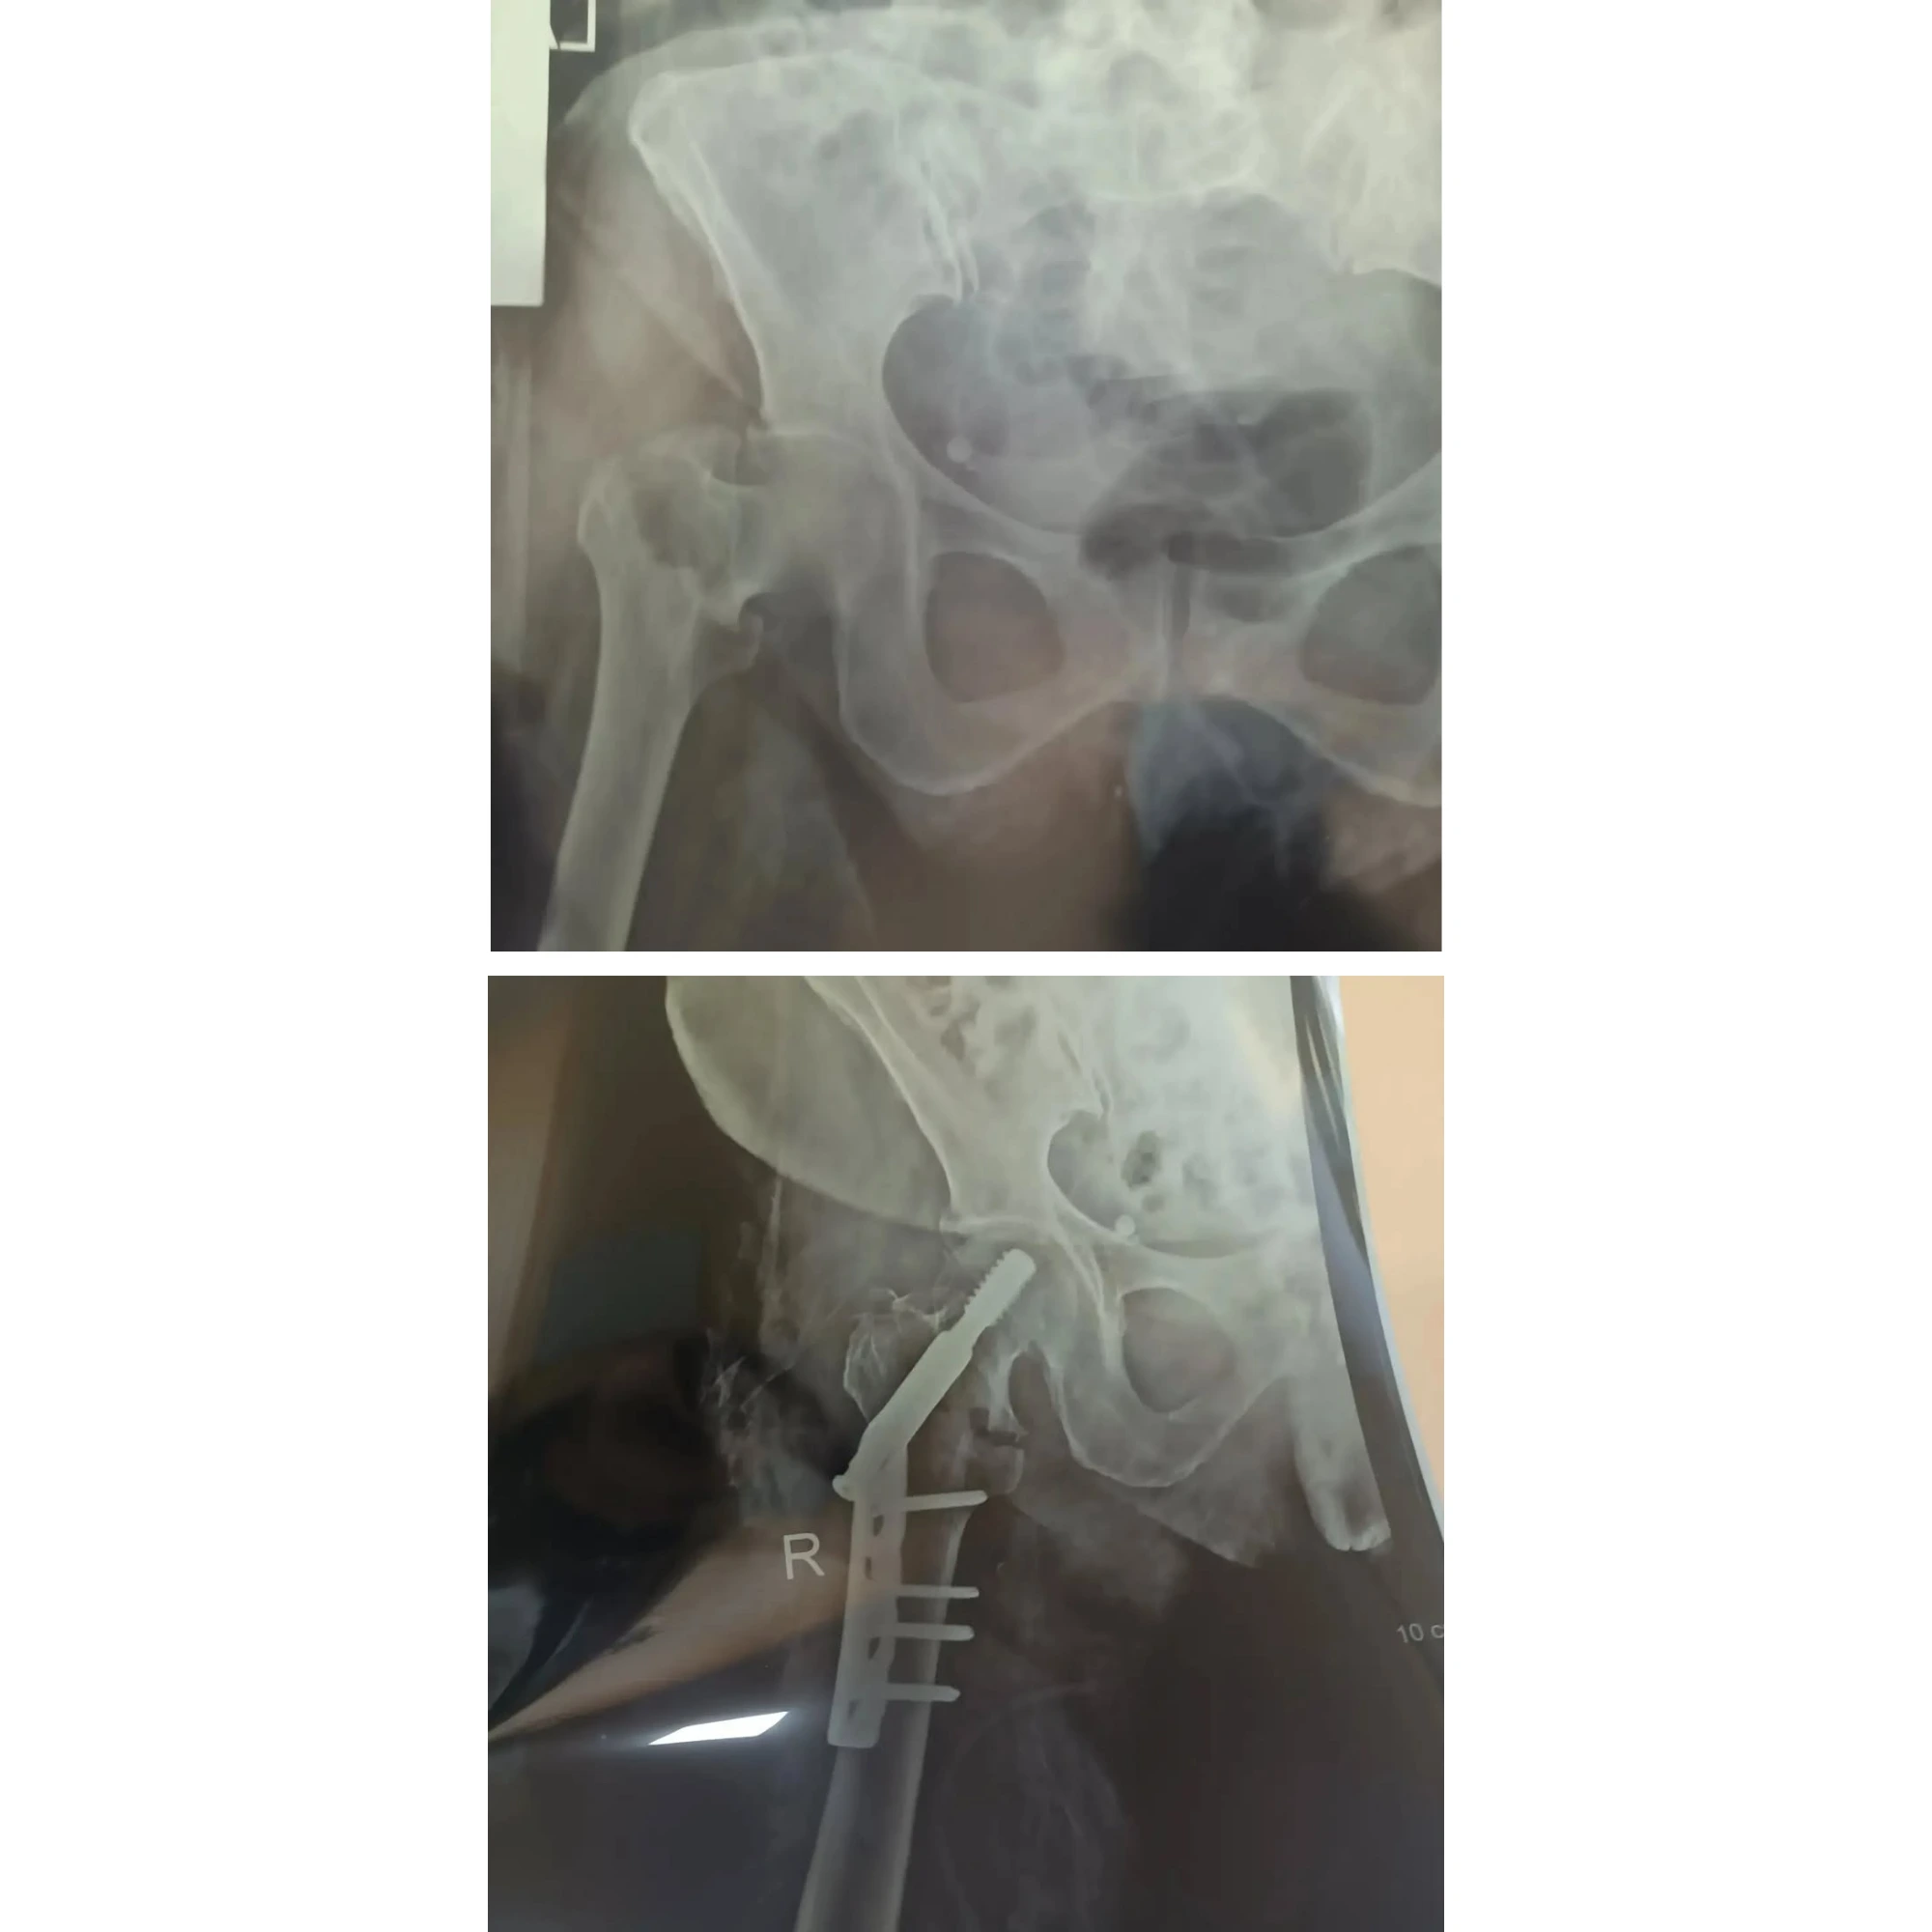

Mürəkkəb sınıqların və oynaq xəstəliklərinin müasir metodlarla bərpasının vizual nəticələri. Pasientlərimizin itirilmiş hərəkət funksiyalarının geri qazanılması bizim ən böyük uğurumuzdur.

Hər bir müalicə prosesi yüksək dəqiqlik və müasir cərrahi standartlara əsaslanır. Bu bölmədə Op. Dr. Aqil Yusubovun əməliyyatxana fəaliyyəti, kliniki iş mühiti və tətbiq etdiyi innovativ metodlarla yaxından tanış ola bilərsiniz.